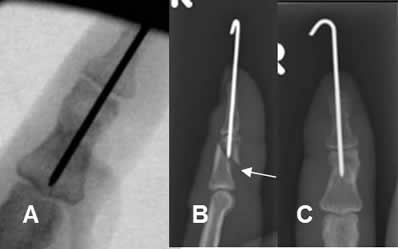

Fig 111. Salida material.

A: Rx AP. PostQx inmediato, con reducción anatómica de fractura en la falange media.

B: Rx lateral y C: Rx AP. Desplazamiento del clavo. No hay contacto entre los extremos y el clavo está por fuera del fragmento proximal.